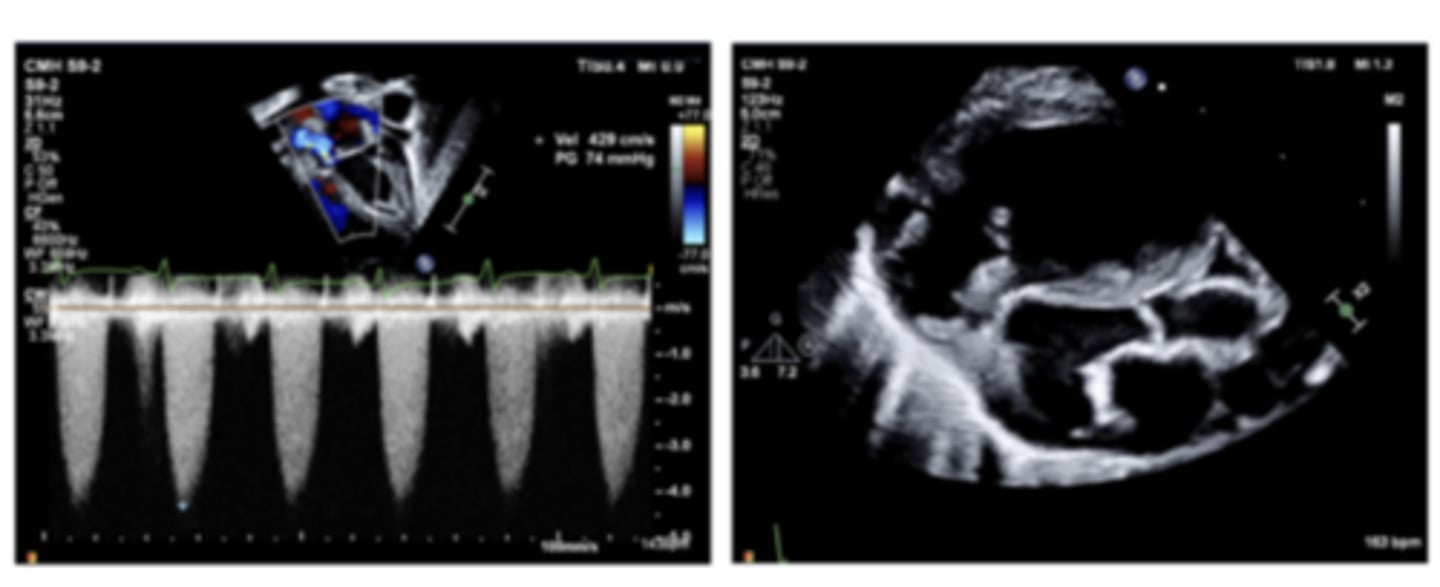

critical AS

WHAT LESION?